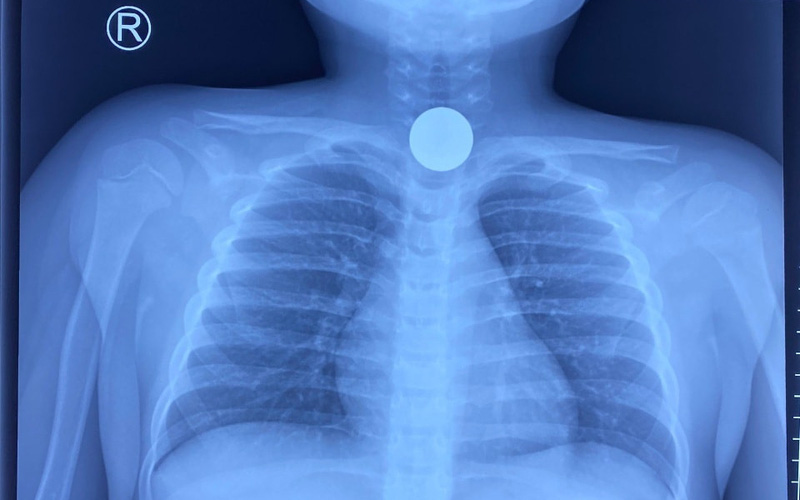

Tại bệnh, các bác sĩ đã cho bệnh nhi chụp X-quang, kết quả trên phim phát hiên có một vật cản âm tròn đều như mô tả đồng xu, mật độ như kim loại.

Do bệnh nhi đã nhịn ăn theo dõi từ trước, các bác sĩ tiến hành nội soi gây mê và gắp kịp thời đồng xu chặn ra khỏi đoạn 1/3 thực quản kịp thời cho bệnh nhi.